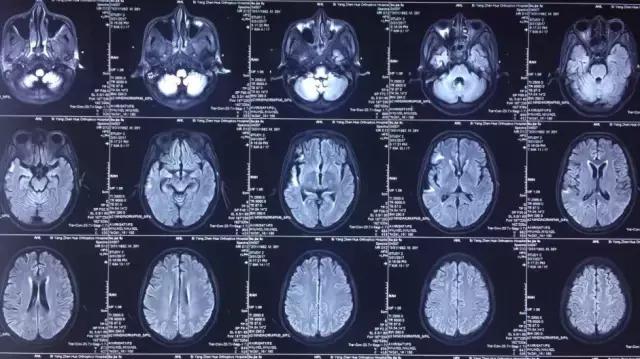

菅老师您好,打扰您了,今天下午做的磁共振,您看一下。

(部分图片)

菅向东教授:

核磁共振看的还可以,这个病人一点儿意识也没有吗?抽搐的话,脑电图对诊断应该有所帮助。